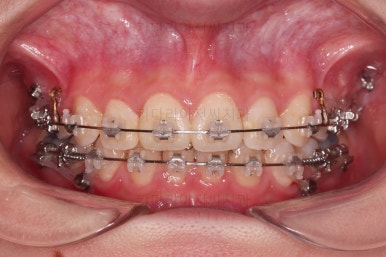

교합이 점점 맞아가네요.

윗니 뽑은 자리도 거의 다 줄었습니다.

교합이 잘 맞아졌고요.

위아래 앞니도 서로 가까워졌어요.

치열도 가지런해졌고, 과개교합도 잘 개선이 되었습니다.